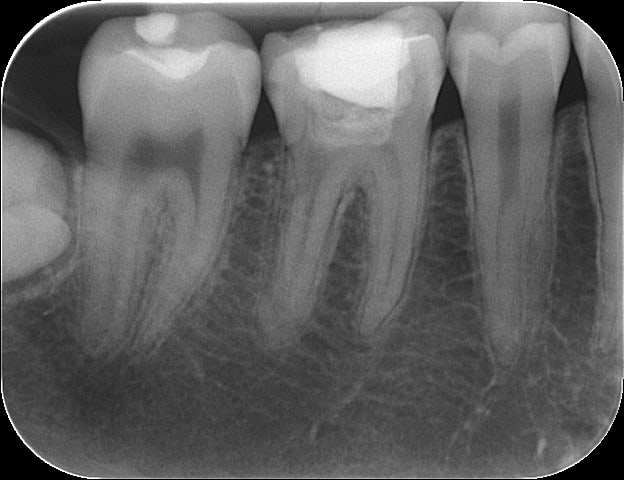

J'ouvre donc la chambre pulpaire, bizarrement ça ne saigne pas tant que ça. Je cathéterise, difficile de trouver les canaux en distale. Mise en place d'OHca.

Je revois la patiente 7 jours plus tard. Elle n'a pas eu de douleurs. Préparation des canaux, toujours des difficultés à trouver l'entrée des canaux en distal surtout le DL.

Je n'arrive pas à obtenir des canaux bien secs, donc OHca.

Quelles chambres pulpaires de fou sur les prémo oO

> Quelles chambres pulpaires de fou sur les prémo oO

19 ans, et c'est un sanguin sans doute ..

Grave quelle chambre de fou sur les prémo!!!...heureusement qu'il n'y a pas de traitement de racine à faire dessus! D'ailleurs je vais soigner la petite carie débutante sur la prémo en distal...

Il y a une possibilité que ce soit un artéfact de la radio. La 6 semble avoir une racine distal bifide, au niveau de la zone de séparation si tu est dans un axe qui sépare légérement les racines l'une de l'autre ça peut apparaître peut radio dense, tu as le même type d'image au 1/3 apical de la 5. Mais la séparation peut aussi se produire beaucoup plus haut et les racine revenir ensuite dans le même axe. Ce n'est pas courant mais ça expliquerait ton image et pourquoi ça n'as pas saigné quand tu as ouvert.